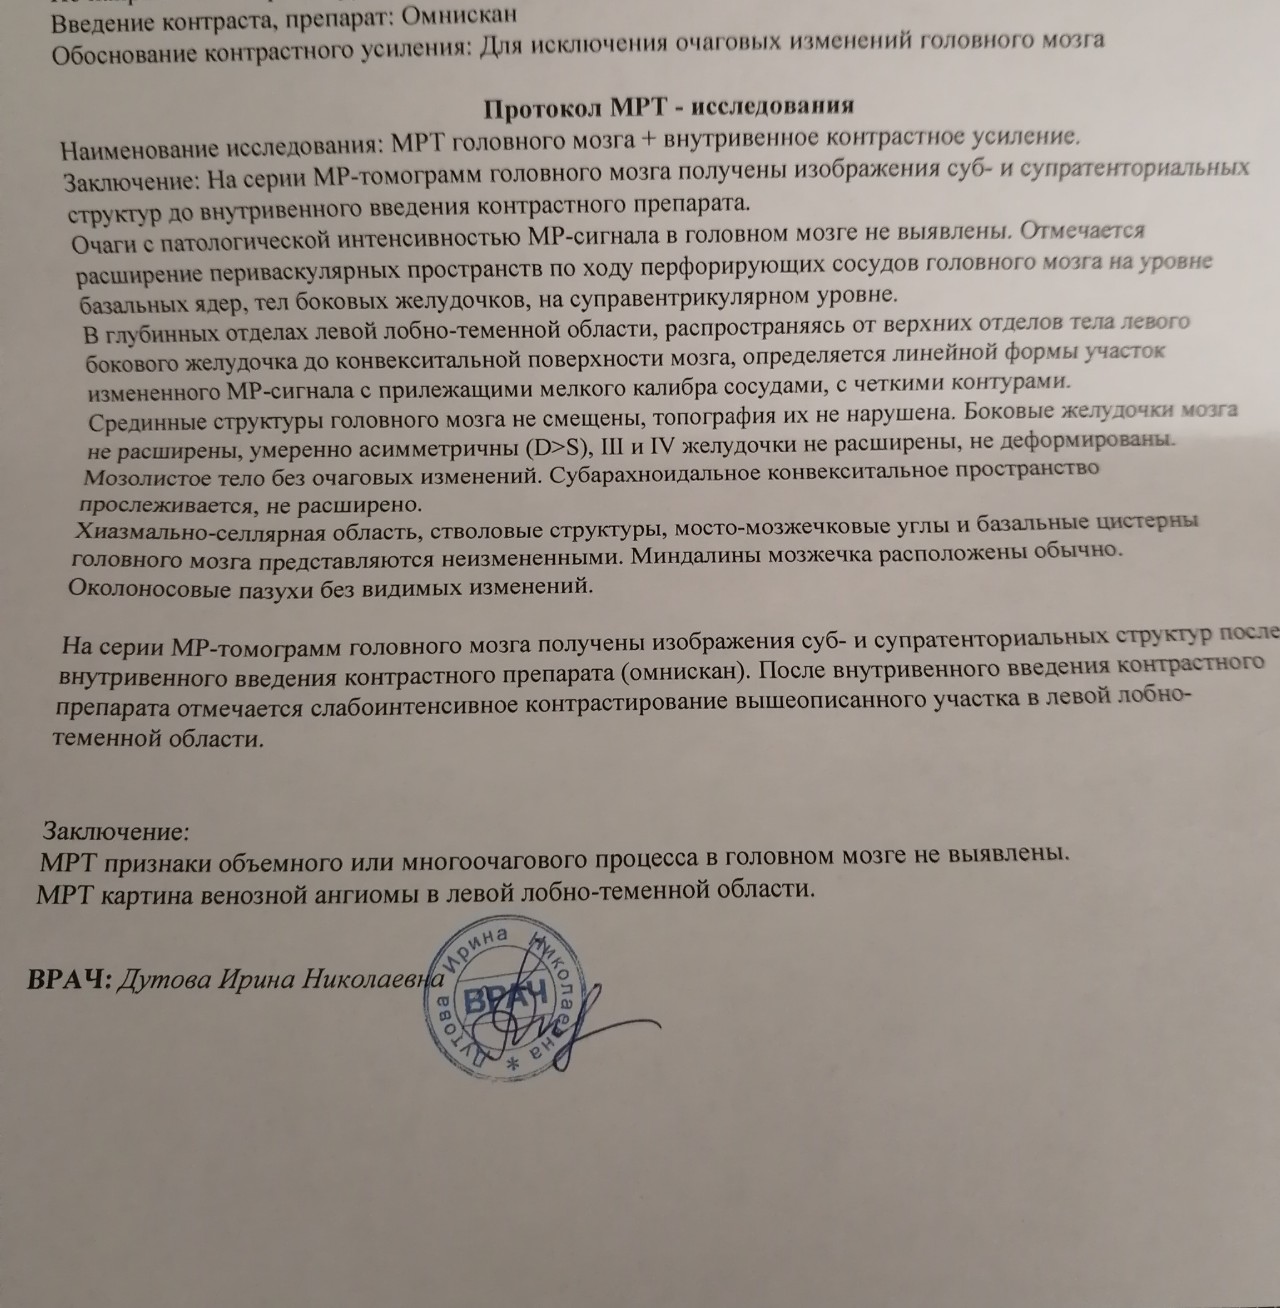

Мр картина венозной ангиомы левой гемисферы мозжечка - 96 фото